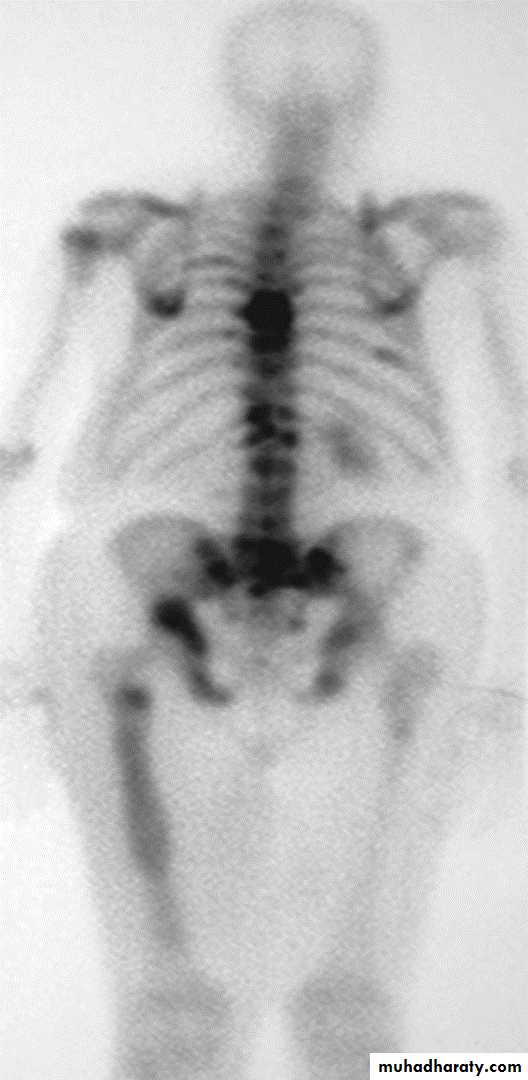

Radionuclide bone scan

Tc99m- labelled with phosphate complex is a bone seeking agent, however it is also taken up by soft tissue calcifications, areas of tissue damage, soft tissue tumors.Given IV and excreted in urine.

Positive scan shown as increased uptake (hot areas): seen in,

trauma, tumor, infection, infarction and Paget's disease.

Correlation with plain radiograph is frequently essential.

Indications: Tc m 99 Phosph

1-Detection of metastases.2-Detection of osteomyelitis.

3-Determination if the lesion is solitary or multiple.

4-Investigation of clinically suspected bone lesion despite normal radiographs (this may occur with metastases, trauma/stress injury, osteoid osteoma or early osteomyelitis).

5- Investigation of painful hip prosthesis.

6-Determination ( in equivocal cases) of whether an abnormality seen on radiograph is significant or not (a positive bone scan makes it likely that a true bone lesion exists and a negative one reduces the probability of disease considerably).